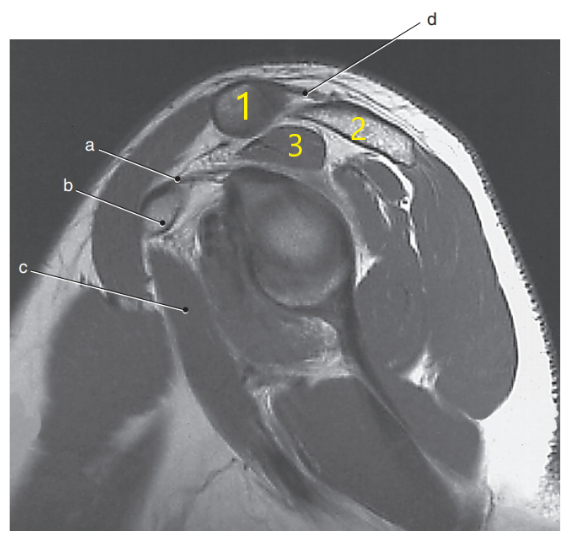

What is letter A pointing to ?

Supraspinatus muscle

What is arrow # 3 ?

Teres minor tendon

What is # 2 ?

Scapula

What is # 3 ?

Acromion Process